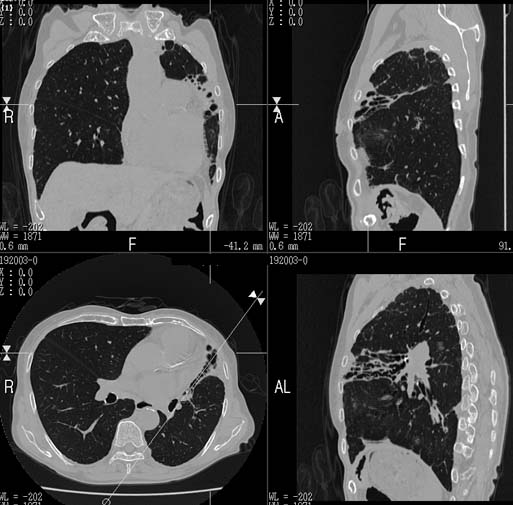

MPR

Data acquired & processed by R. Kato M.D.